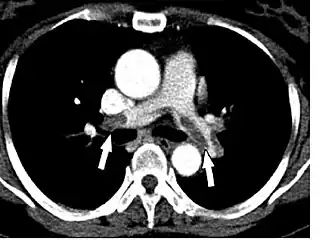

![]() TAC helicoidal con contraste en el que se aprecian defectos de replección en las ramas principales de las arterias pulmonares, debido a embolismos crónicos y agudos. | ||